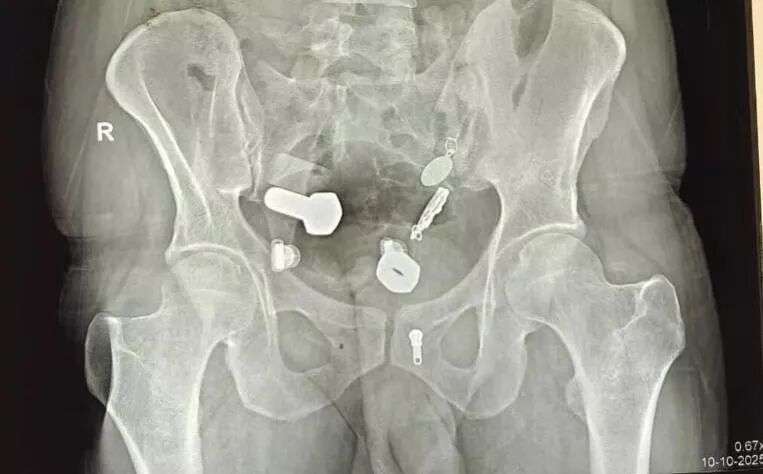

按常规流程,医生给他开了影像学检查,结果拍完片子,大家都惊呆了。

他的消化道简直能开家五金店:螺母、螺栓、金属棒、铁钉、别针......什么都有,而且它们都已经随肠胃运动来到了大肠里,估计已经吞下很久了。

(医学影像)

最离谱的是,还有一只腕表死死地卡在他的食道内部,

这也正是他不吃不喝的原因,不是他不想,是他实在吞不下了......